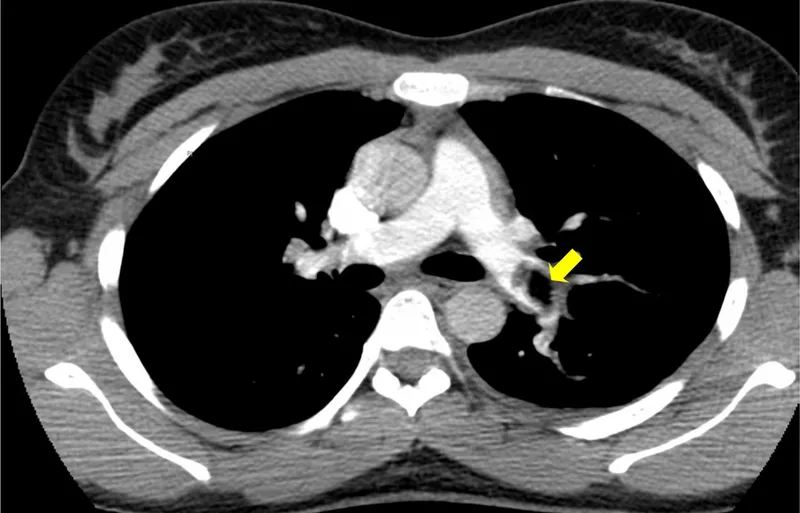

A 45-year-old presents with sudden-onset first metatarsophalangeal joint pain, erythema, and inability to weight-bear. Serum urate is 520 μmol/L, and joint aspiration reveals negatively birefringent needle-shaped crystals-confirming gout . Meanwhile, a 72-year-old with breathlessness has Wells score 6.5 (PE likely); D-dimer is 850 ng/mL, and CTPA confirms segmental pulmonary embolus . These cases demonstrate guideline-concordant diagnostic pathways.

VTE diagnosis (NICE NG158):

Early aggressive DMARD therapy in follows NICE NG100: methotrexate 15-25 mg weekly with folic acid 5 mg weekly (not on methotrexate day) is first-line. Treatment target is remission (DAS28 <2.6) or low disease activity. Failure after 3 months at therapeutic dose warrants escalation to dual/triple DMARD or biologic therapy (anti-TNF, rituximab, tocilizumab). For VTE , NICE NG158 recommends DOACs (apixaban 10 mg BD for 7 days, then 5 mg BD) over warfarin for most patients.